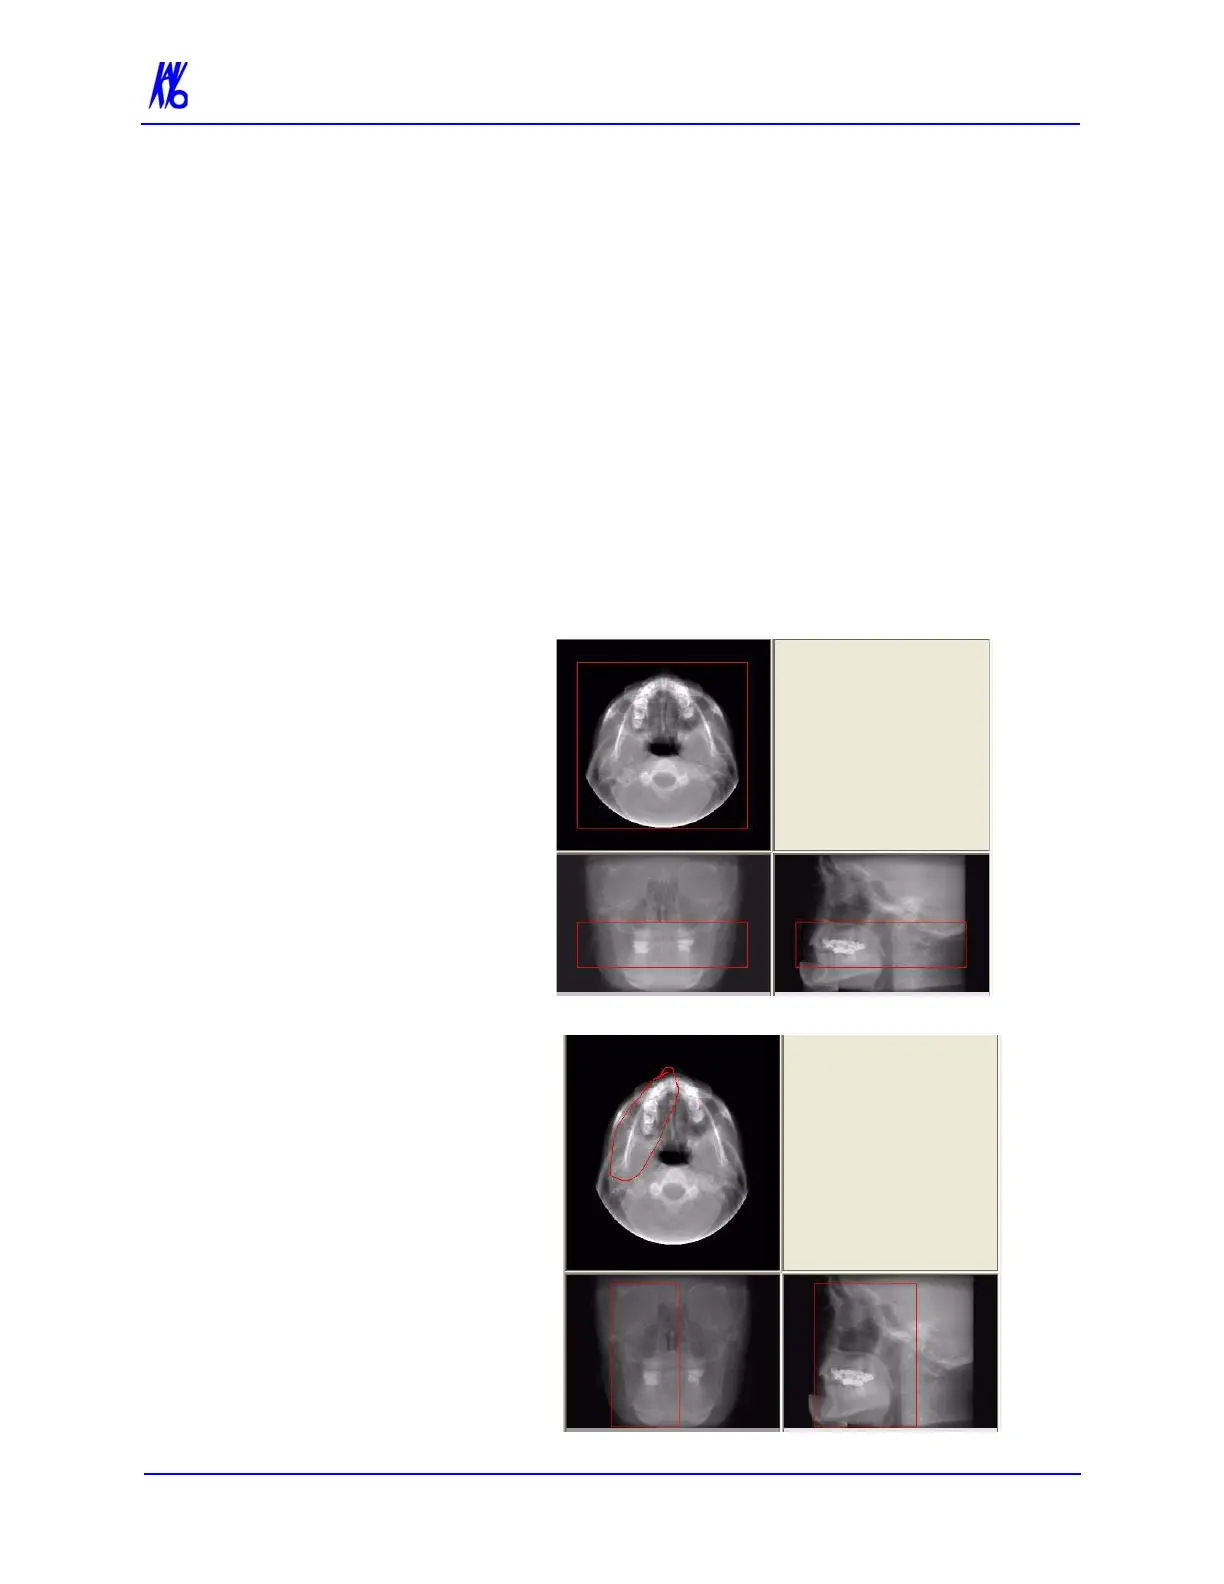

Volume Editing is used to select an area of interest to create a 3D

rendering. The two methods used are Box and Freehand.

Box - with this option, each of the 3 views are displayed

with a red box around the data. Boxes can be resized to

select different areas of interest.

Freehand - drag the cursor around an area of interest in the

Axial view (see below). This selects a new area of interest

in the Coronal and Sagittal views.

Box Editing

Freehand Editing

In this sample, we resized

the box from the Coronal

view to include only a

portion of the upper and

lower jaw. Note how this

resized the matching area

in the Sagittal view.

In this sample, we used the

Freehand tool to draw an area

of interest in the Axial view

of only the right side of the

jaw. Notice how the boxes

resized the matching areas in

the Coronal and Sagittal

views.